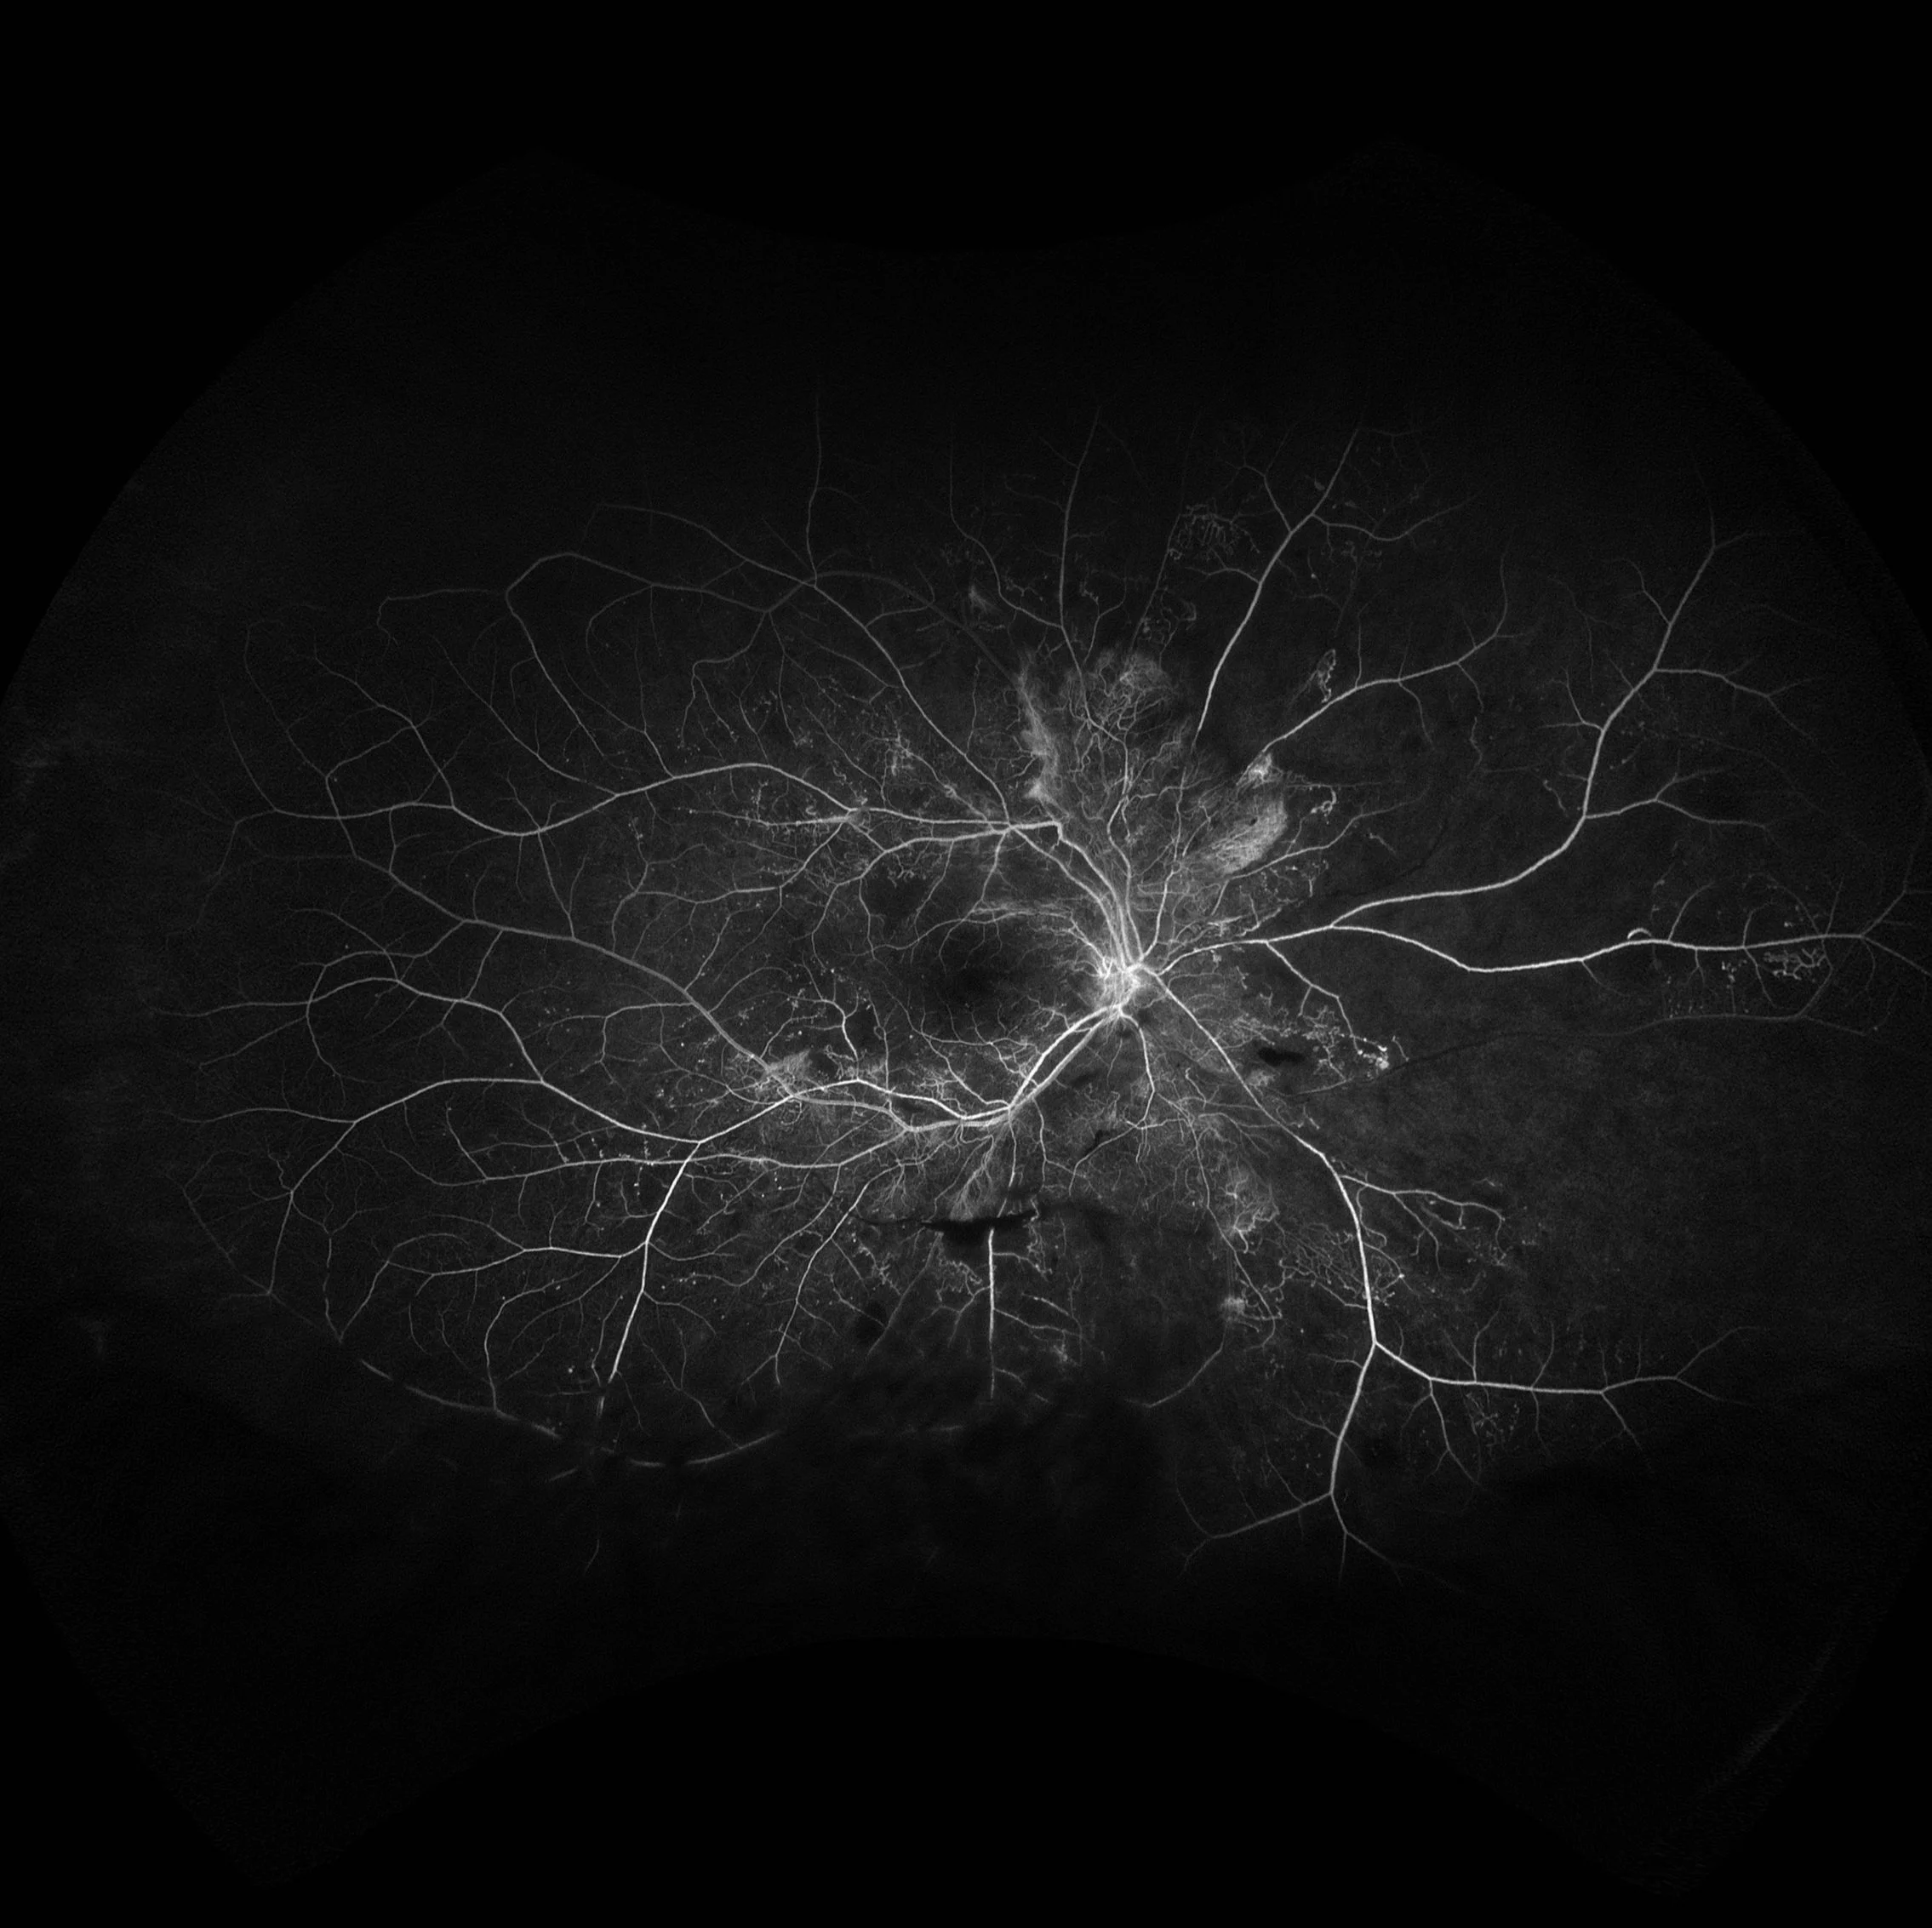

Hyperfluorescence Case #1

Reason for Referral: Diabetic Retinopathy Check

Past Ocular History: PDR, with a history of IVI

Past Medical History: Type 2 Diabetes Mellitus (HbA1c 12.3%)

• Retinal neovascularization secondary to proliferative diabetic retinopathy.

Areas of hyperfluoresence in this IVFA are due to neovascularization and associated leakage of the vessels. Notice the neovascularization elsewhere and the neovascularization of the disc. Hypofluoresence in this IVFA is due to vitreous hemorrhage.